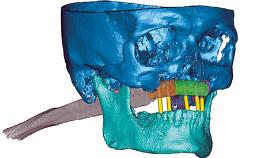

Immediate Loading of an Anterior Implant with a Prefabricated Crown

A fully digital workflow for a patient with adequate bone but soft tissue defects is outlined in this case. Key features include: Use of the CAD software’s mirroring feature to create the digital diagnostic wax-up, a CAD/CAM custom zirconia abutment and PMMA provisional crown, connective-tissue grafting performed at the time of implant placement, and modification of the provisional crown to shape the emergence profile and change the position of the labial mucosal margin to better match the contralateral tooth.